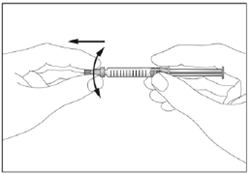

9. Entfernen Sie die Kappe von der Fertigspritze (siehe Abbildung 2).

2